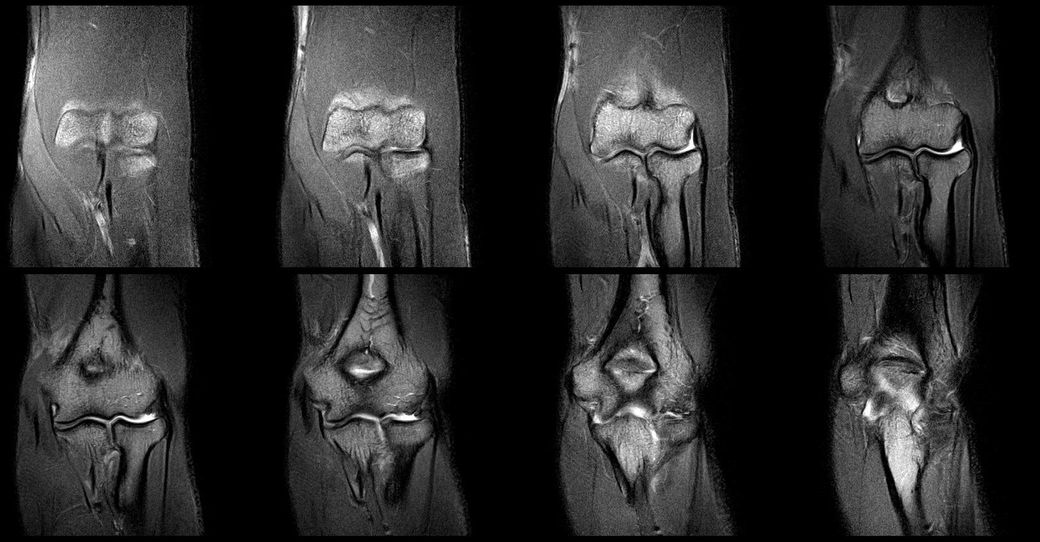

- MRI: 좌측 삼두건 경미한 염증, ulnar nerve supracondylar level 경미한 신호 증가

아래는 관련 사진 첨부합니다.

• 1번 째 사진

• 2번 째 사진

• 3번 째 사진

• 4번 째 사진

• 5번 째 사진